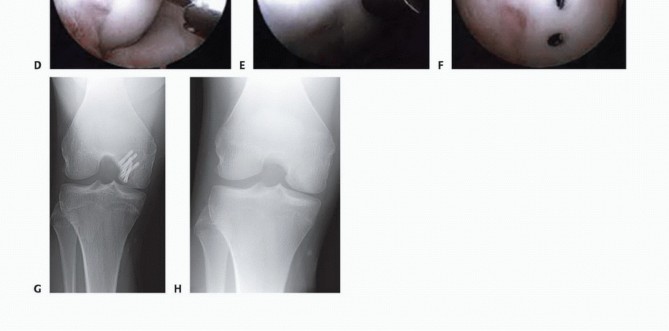

FIG 5 • A. Fragmentation of the distal femoral condyle with multiple loose bodies. B. After débridement of the femoral condyle and removal of loose bodies. C. Fragments after arthroscopic removal. (Reprinted with permission from Diduch DR, Hampton BJ. Avascular necrosis drilling in the knee. In: Miller MD, Cole BJ, eds. Textbook of Arthroscopy. Philadelphia: Elsevier, 2004:593-599.)

In general, only AVN involving the epiphysis is clinically important. Here, loss of structural support can lead to collapse and fragmentation of the overlying joint surface, resulting in a painful arthritic joint (

FIG 5

*).

Drilling can be accomplished using either an antegrade or retrograde technique ( TECH FIG 1A ).

Antegrade techniques are technically easier but violate the articular cartilage.

Retrograde techniques avoid violation of the articular surface but involve the technical challenges of maintaining drill depth and placement accuracy and also require the use of fluoroscopy. A cannulated anterior cruciate ligament (ACL) guide is useful for guiding Kirschner wire placement.

TECH FIG 1 • A. Retrograde and antegrade drilling of OCD lesions. B. Probe seen indenting the edge of an OCD lesion.

First, a thorough diagnostic arthroscopy is completed.

Careful inspection of the affected condyle is accomplished by varying the degree of knee flexion. Subtle irregularity at the borders of the lesion is looked for; the remaining articular cartilage will appear smooth.

The lesion is probed along its borders to ensure that there are no discontinuities in the articular cartilage overlying the subchondral bone ( TECH FIG 1B ).

Once the presence of an intact lesion has been verified, several drill holes are made in the lesion using a 0.062-inch Kirschner wire ( TECH FIG 1C,D ).

The wire must be positioned perpendicular to the surface. A soft tissue protector or drill sleeve is used over the wire.